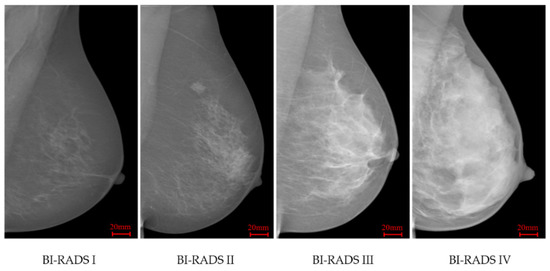

According to BI-RADS (4th edition) [6], breast density classification depends on the proportion of dense fibro-glandular tissue within the breast area in mammograms. The four categories are: (a) BI-RADS I (0–25% dense tissue, predominantly fat); (b) BI-RADS II (26–50% dense tissue, fat with some fibro-glandular tissue); (c) BI-RADS III (51–75% dense tissue, heterogeneously dense); and (d) BI-RADS IV (above 75% dense tissue, extremely dense). In many countries, radiologists estimate mammographic density using visual assessment, leading to the inter- and intra-readers variability [8].

INbreast [34] is a FFDM database which contains 115 cases and 409 images including bilateral mediolateral oblique (MLO) and craniocaudal (CC) views. This database was acquired at the Breast Centre in CHSJ, Porto, under permission of both the Hospitals Ethics Committee and the National Committee of Data Protection. The images were acquired between April 2008 and July 2010; the acquisition equipment was the MammoNovation Siemens FFDM, with a solid-state detector of amorphous selenium, pixel size of 70 mm (microns), and 14-bit contrast resolution. The image matrix was 3328 × 4084 or 2560 × 3328 pixels, depending on the compression plate used in the acquisition (based on the breast size of the patient). This dataset offers carefully associated ground truth (GT) annotations by radiologists. For breast density, BI-RADS labels are available, including 136, 146, 99 and 28 images respectively in BI-RADS I to IV classes. Figure 1 illustrates four INbreast mammograms in different density categories.

Figure 1. INbreast mammograms in four different breast density categories.